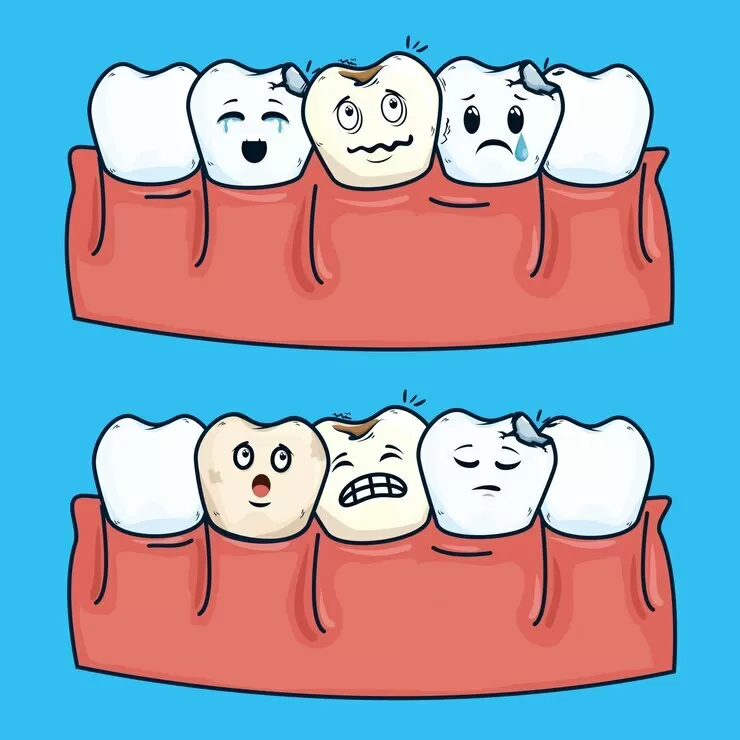

Степени развития

- ранний, который получил название «кариозное пятно» («macula cariosa»),

- поверхностный («caries superficialis»),

- средний («caries media»),

- поздний, который получил название «глубокий кариес» («caries profunda»).

На каждом этапе развития заболевание имеет свои симптомы и свои способы лечения.

Ранний на стадии кариозного пятна

Ранний кариес на стадии кариозного пятна, как правило, остается незамеченным пациентом. Ведь мало кто обратит внимание на появление небольшого белого пятнышка на зубной эмали, при этом пациент совершенно не испытывает дискомфорта. На самом деле, это маленькое пятнышко и есть самый настоящий кариес. И если его вовремя не лечить, можно потерять зуб.

Поверхностный

Имеет ярко выраженные симптомы. Пятно на зубной эмали становится бурым и шероховатым, а сам зуб — чувствительным. При употреблении горячей или холодной пищи зуб может реагировать острой болью, которая со временем утихает. Не следует обманывать себя — если зуб начал болью реагировать на прием пищи, необходимо срочно записаться на прием к стоматологу.

Средний

Наиболее распространен. Именно на этой стадии пациенты чаще всего и обращаются к врачу за помощью. На этой степени развития кариозная полость затрагивает не только зубную эмаль, но и дентин. Зуб становится чувствительным и реагирует болью не только на горячее или холодное, но и на прикосновение. Зачастую на этой стадии любой прием пищи превращается в болезненный процесс.

Глубокий

Поражается практически весь слой дентина больного зуба, а сам зуб становится хрупким и может полностью разрушиться. Лечится успешно, однако само лечение более длительное и часто включает в себя удаление зубного нерва. Самым неприятным осложнением глубокого кариеса является пульпит, или воспаление пульпы.